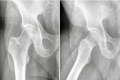

Introduction: The pelvic digit or pelvic rib is an unusual congenital anomaly with a finger or rib like bone formation in soft tissues around normal pelvic skeleton. This is a benign lesion and mostly an Incidental finding on radiographs. Most reported cases are asymptomatic and do not require intervention. We report a case of symptomatic pelvic rib that required surgical excision.

Case report: A 57-year-old man presented with a long history of pain and functional limitation in his right hip. On plain radiographs a fusiform bony structure adjacent to the acetabulum was noted. The imaging tests (MRI and CT) suggested the diagnosis of pelvic digit. We performed surgical excision of the lesion through anterior Smith-Peterson approach. The histopathology showed presence of corticomedullary structure. After surgery the patient's symptoms were relieved.

Conclusions: It is important to recognize this lesion on plain radiographs and to confirm by CT scan and make differential diagnosis. In the majority of cases the pelvic digit is asymptomatic and no treatments is needed. However in cases where symptoms can be attributed to pelvic digit an excision will relieve the pain and disability.